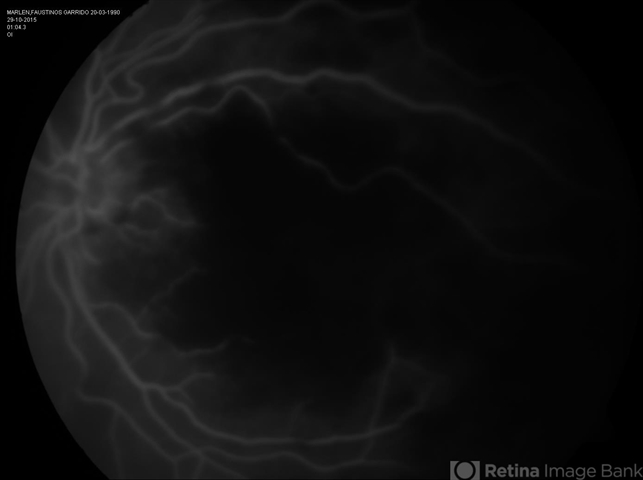

- LUPUS RETINOPATHY

- systemic lupus erythematosus (SLE) retinopathy

- FA in a female with 21-year-old with LES after pregnancy.